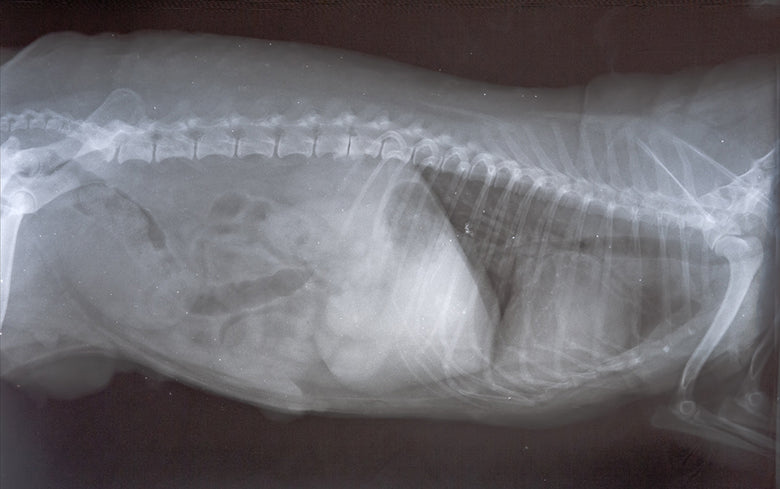

Ma petite caniche a 18 ans. Le lendemain du vaccin contre la rage elle s est mise à tousser par quinte de toux sèche caverneuse. Une masse médiastinale à été détectée à la radio. L insuffisance rénale minime à repris du service. Elle est sous antibio en espérant que c un ganglion qui a flambe. Dois je lui faire passer un scanner pour en savoir plus ou est ce risque avec une insuffisance rénale ? Après le scanner puis je faire chirurgie chimio ou autre avec une chienne de 18 ans. Merci de votre aide. Si vous avez un remède…